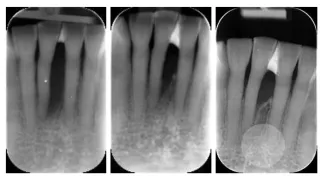

Bildet viser 3 stadier i regenerasjonsterapi.1) En fortann i underkjeven mangler ben helt ned til rotspissen2) Det er gjort en regenerasjonsterapi men bare med begrenset effekt3) Regenerasjonsterapien er gjentatt med svært godt resultat. Både ben og tannfesteer gjendannet

Periodontal regenerasjonsterapi

Det forskes mye på gjenoppretting av tannfestet som er tapt på grunn av periodontitt. Selv om dette er mulig i enkelte tilfeller, er det ofte uforutsigbart og skjer som regel i begrenset grad. Dette kalles regenerasjonsbehandling og gjøres ved bruk av spesielle kirurgiske teknikker. Denne behandlingen er ofte den samme som for kirurgisk periodontittbehandling der man åpner en tannkjøttslapp, renser rotoverflaten og fjerner betennelsesvev. I tillegg introduserer man ulike materialer som skal stimulere kroppen til å gjenskape det som tidligere er nedbrutt av periodontitt: nytt kjevebein, periodontalligament ( Sharpeys fibre ) og rotsement.

Ekte regenerasjon er vanskelig å oppnå fordi man er avhengig av å gjenskape alle disse tre ulike vevene på samme tid.